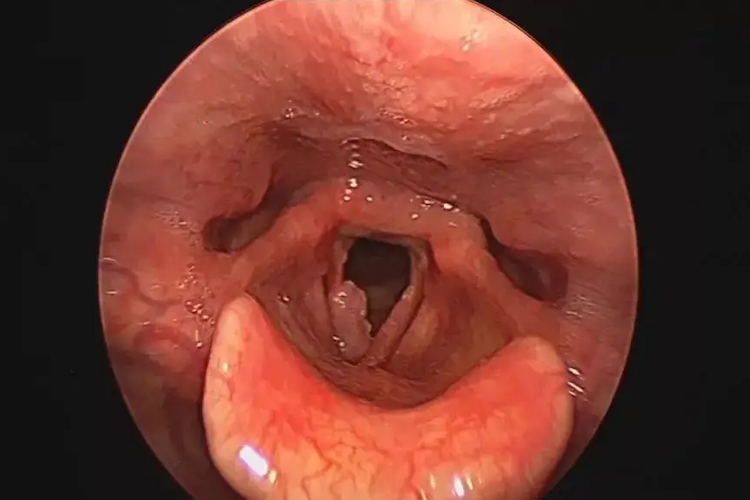

声门型喉癌1例

我院耳鼻喉科成功完成内镜支撑喉镜低温等离子声门型喉癌切除术

喉癌 b.会厌癌 c.声带癌 d.声门下区癌 e.跨声门型癌